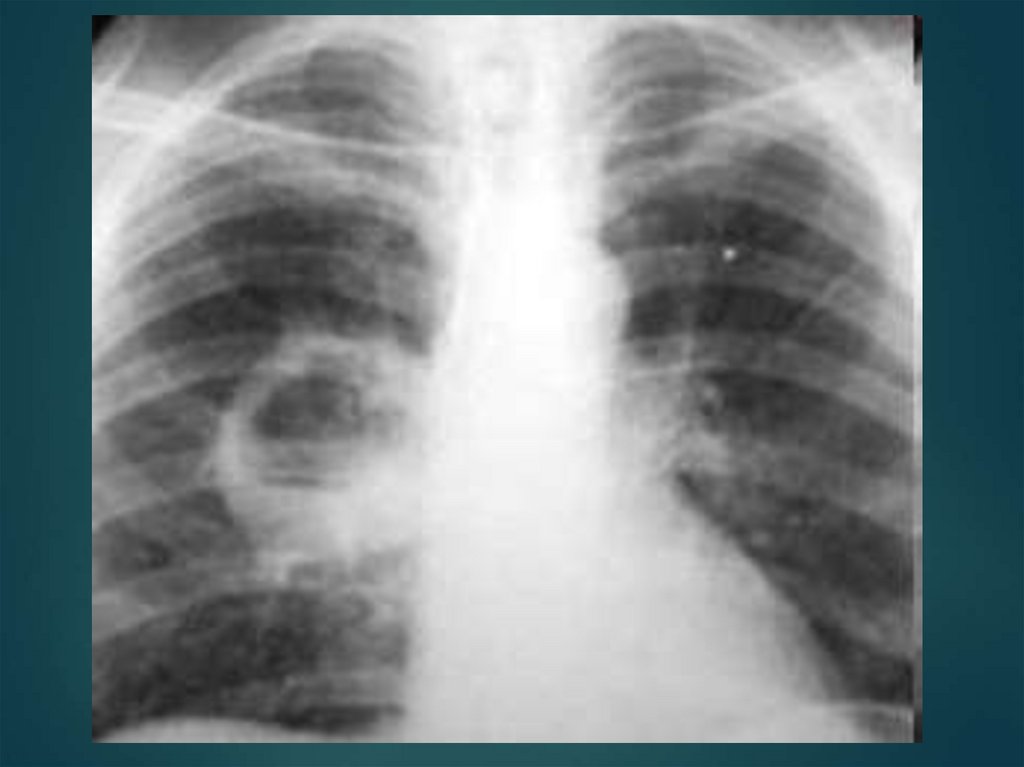

Абсцесс лёгкого - инкапсулированная гнойная полость, окружённая зоной воспаления.

85. Абсцесс лёгкого - инкапсулированная гнойная полость, окружённая зоной воспаления.

Лихорадка (постоянная или

интермиттирующая), недомогание

Боли в груди

Кашель

Потеря аппетита, потливость

Обильное выделение гнойной мокроты (в

результате прорыва гнойника в бронх)

Расслоение отстоявшейся мокроты на 3 слоя

Состояние больного после прорыва

абсцесса улучшается